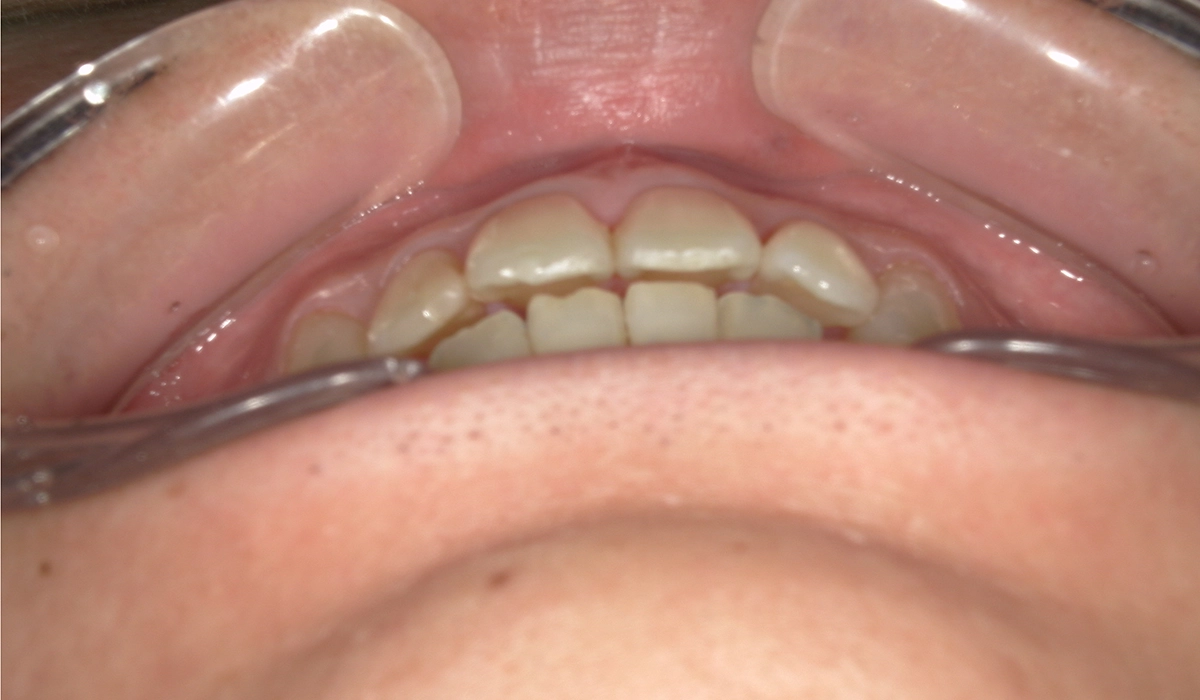

術前:オーバージェット

術後:オーバージェット